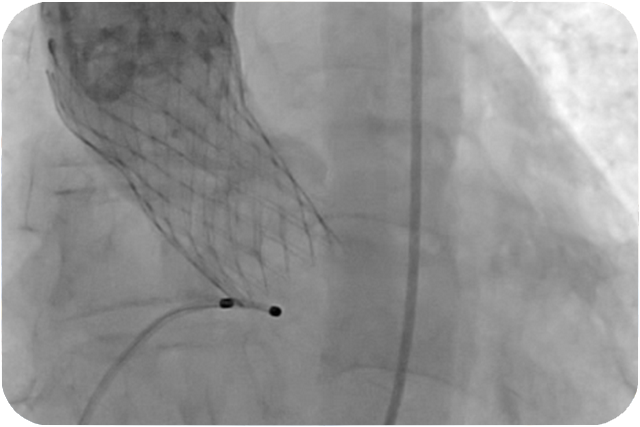

提供:エドワーズライフサイエンス(株)・メドトロニック(株)

いくつかの方法がありますが、95%以上は、足の付け根(ソケイ部)の大腿動脈からカテーテル(医療用のチューブ・管)を挿入して、大血管を通じて、大動脈弁の中に人工弁を留置する方法です。